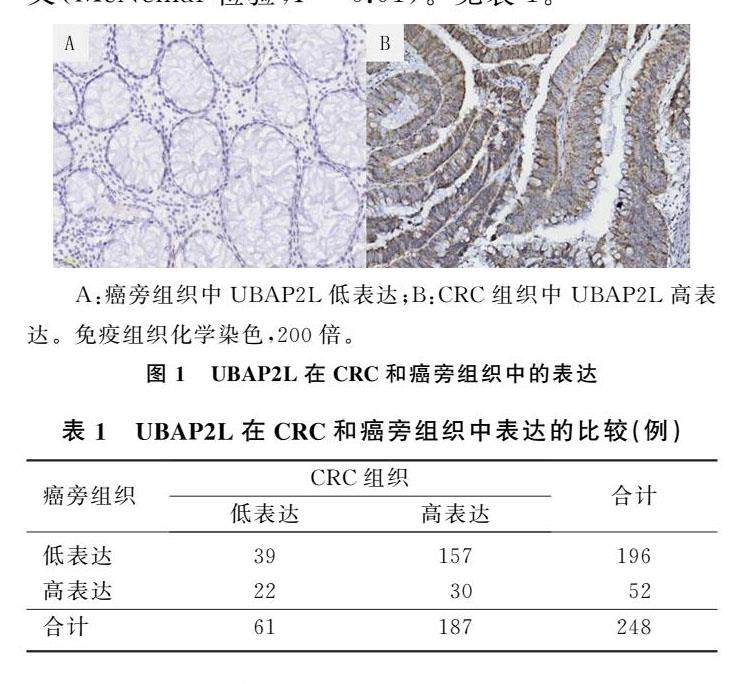

论著 | UBAP2L在结直肠癌中的表达及其意义

论著 | UBAP2L在结直肠癌中的表达及其意义